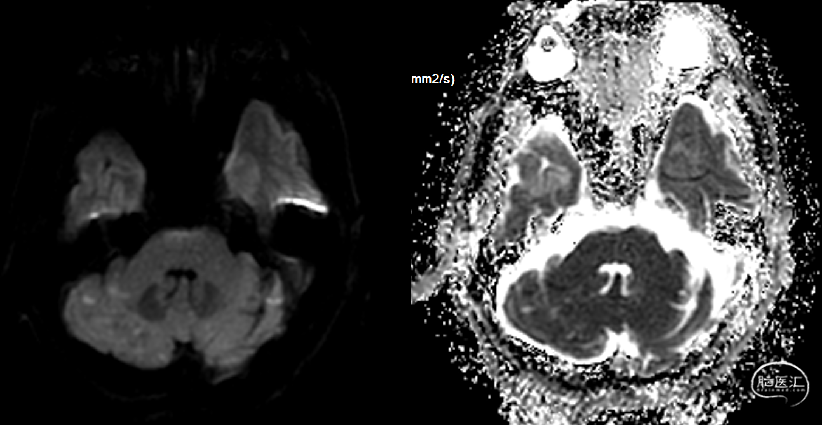

头颅核磁提示:右侧大脑半球、双侧小脑半球多发散在DWI高信号,考虑急性亚急性脑梗死;头颅MRA未发现明显重度狭窄及闭塞大血管。